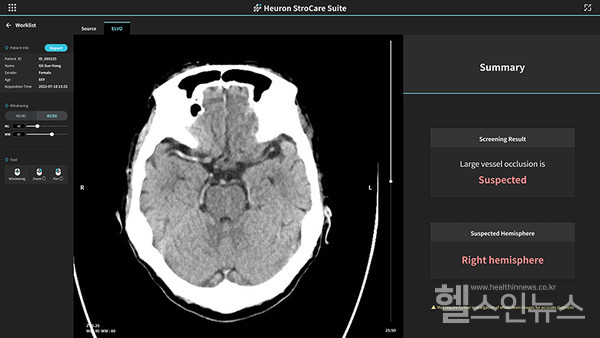

최근 이 혁신의료기술로 선정된 휴런 스트로케어 스위트는 비조영 CT를 기반으로 환자의 ▲출혈성 뇌졸중 의심여부 ▲응급 뇌 대혈관 폐색 의심 여부 ▲초기 허혈성 변화점수 등을 제공해 의사의 진단과 치료 방향 설계를 보조하는 인공지능 솔루션이라고 회사측은 설명했다.

혁신의료기술전문위원회는 평가보고서를 통해 “뇌졸중은 국내 사망률 5위 안에 포함될 정도로 높은 사망률을 보이는 중증 질환이며 생존 시에도 영구적인 장애를 남긴다”며 “‘비조영 증강 CT 영상 분석을 통한 뇌 대혈관 폐색 의심 여부 제공은 추가 검사 방지 및 처치 시간 단축 등을 통해 환자의 신체적 부담 감소 및 예후 향상에 도움이 될 가능성이 있다”는 의견을 밝혔다.

특히나 휴런 스트로케어 스위트는 영상의학과, 신경과 등의 전문의가 없는 응급실에 환자가 내원한 경우 진료 업무 흐름과 환자 처치 신속성 개선을 이끌어내 의료기관별 의료를 격차를 해소하는 데에 유용성이 있다는 점에서 높은 평가를 받았다는 회사측의 설명이다.